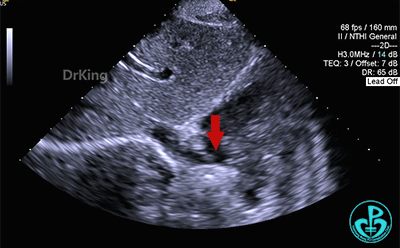

固定钢缆,前抵鞘管,牵拉成型线锁定(左),锁定后牵拉试验(右),封堵器位置固定,未见明显位移及形变。

剑下双房心、四腔心切面观察封堵器,位置正确、形态良好。

剑下双房心切面显示封堵器呈夹持稳定。